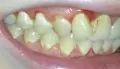

Волнуют мои зубы. Мне кажется, что мои зубы находятся в крайне запущенном состоянии. Как привести мои зубы в приемлемый вид? Мне кажется, что запломбированные зубы плохо выглядят. На верхней левой четверке выпала пломба.

Ваши зубы скорее всего требуют срочного лечения. Где-то возможно хроническое воспаление (периодонтит), а где-то и пульпит (воспаление нерва).